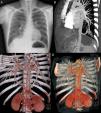

En la consulta de revisión persistía parcialmente la masa homogénea derecha, y se observó una «opacidad tubular» en base izquierda detrás de la silueta cardiaca (fig. 1A) que nos orientó al diagnóstico de secuestro pulmonar, por lo que solicitamos una angiotomografía, con los hallazgos de secuestro pulmonar (SP) derecho en localización basal posterior, sin cisura de separación con el resto del parénquima pulmonar, irrigado por una arteria que procede de la aorta abdominal, el drenaje venoso va a la aurícula izquierda a través de la vena pulmonar inferior derecha; SP izquierdo en localización basal posterior, cisura de separación parcial con el resto del parénquima pulmonar, irrigado por una arteria procedente de la aorta torácica, el drenaje venoso va a la aurícula izquierda a través de la vena pulmonar inferior izquierda (figs. 1B-D).

A) Radiografía de tórax PA donde se observa una masa bien definida en LID, sin aparente broncograma aéreo en su interior, y una opacidad tubular retrocardiaca izquierda que corresponde a un vaso nutricio proveniente de una rama de la aorta abdominal. B-D) Reconstrucción de la TC de tórax donde se evidencian los vasos que nutren ambos secuestros. En el derecho se observa la arteria proveniente de la aorta abdominal con su drenaje venoso a aurícula izquierda, a través de la vena pulmonar inferior derecha. En el izquierdo se visualiza la arteria proveniente de la aorta torácica con su drenaje venoso a aurícula izquierda, a través de la vena pulmonar inferior izquierda.